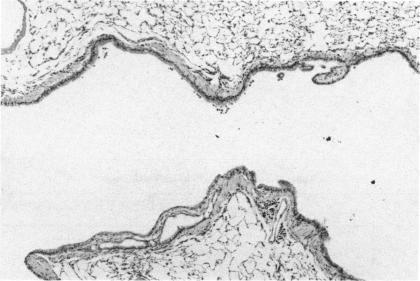

B6C3F1 mice were exposed by inhalation to 0, 3, 10, and 30 ppm methyl isocyanate for 2 hr followed by a 90-day recovery period. Sixteen of eighty (20%) male mice in the 30 ppm group died following exposure. There were no other unscheduled deaths in the mice. Five mice/sex/group were examined at 2 hr or at 1, 3, 7, 14, 28, 49, or 91 days following exposure. Chemical-related changes were restricted to the respiratory system. At 30 ppm there were extensive necrosis and erosion of the respiratory and olfactory epithelium in the nasal cavity. Severe necrosis and epithelial erosion were also found in the trachea and main bronchi. Regeneration of the mucosal epithelium occurred rapidly in the nasal cavity and airways. In the turbinates, mild incomplete olfactory epithelial regeneration persisted to day 91 in the male mice. Intraluminal fibrotic projections covered by respiratory epithelium and bronchial fibrosis were found in the major airways of the 30 ppm male and female mice by day 7. The intraluminal fibrosis persisted to day 91. In males with severe bronchial fibrosis, chronic alveolitis and atelectasis were found. In mice exposed to 3 or 10 ppm, persistent pulmonary changes were not found. These studies indicate that methyl isocyanate inhalation at or near lethal concentrations can cause persistent fibrosis of the major bronchi in mice.

将B6C3F1小鼠通过吸入方式暴露于浓度为0、3、10和30 ppm的异氰酸甲酯中2小时,随后进行90天的恢复期。在30 ppm组的80只雄性小鼠中有16只(20%)在暴露后死亡。小鼠中未出现其他意外死亡情况。在暴露后2小时或1、3、7、14、28、49或91天,对每组5只/性别小鼠进行检查。与化学物质相关的变化仅限于呼吸系统。在30 ppm时,鼻腔内的呼吸和嗅觉上皮出现广泛坏死和糜烂。气管和主支气管也发现了严重坏死和上皮糜烂。鼻腔和气道内的黏膜上皮迅速再生。在鼻甲中,雄性小鼠的轻度不完全嗅觉上皮再生持续到第91天。到第7天时,在30 ppm的雄性和雌性小鼠的主要气道中发现了被呼吸上皮覆盖的腔内纤维化突起和支气管纤维化。腔内纤维化持续到第91天。在患有严重支气管纤维化的雄性小鼠中,发现了慢性肺泡炎和肺不张。在暴露于3或10 ppm的小鼠中,未发现持续性肺部变化。这些研究表明,吸入接近或达到致死浓度的异氰酸甲酯可导致小鼠主要支气管的持续性纤维化。